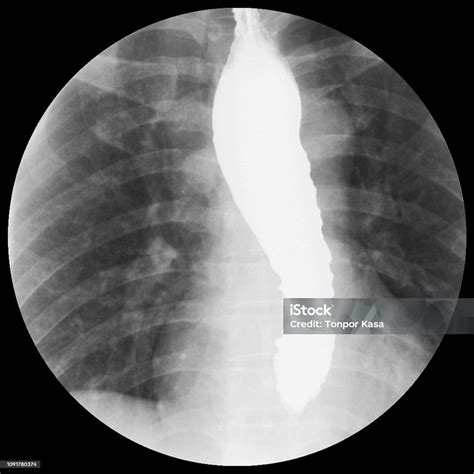

The hallmark finding on a barium swallow study for achalasia is the "bird’s beak" appearance. This occurs because the LES remains tightly closed, causing the esophagus above it to dilate and taper to a narrow point, resembling the beak of a bird. This visual evidence is often the first major indicator that confirms a diagnosis of achalasia.

When a patient presents with dysphagia (difficulty swallowing), the Achalasia Barium Swallow serves as a cornerstone diagnostic test. During this procedure, the patient drinks a liquid containing barium, a contrast material that coats the inner lining of the esophagus. As the patient swallows, a radiologist uses fluoroscopy—a continuous X-ray beam—to observe the movement of the liquid down the esophagus in real-time.

Achalasia Barium Swallow Structural/Functional observation High; identifies "bird's beak" and esophageal dilation.